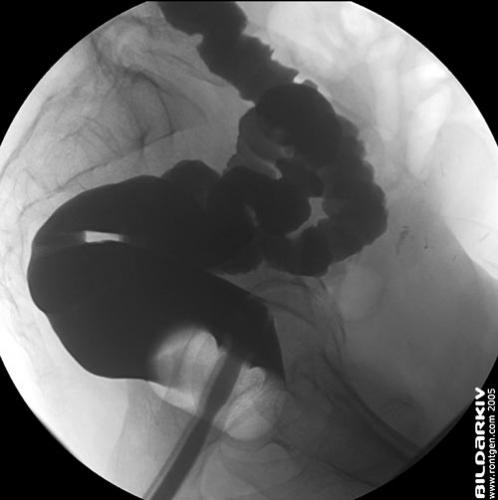

Sidobild ändtarmen med uppblåsbar colon-pip. Enkelkontrast infunderad.